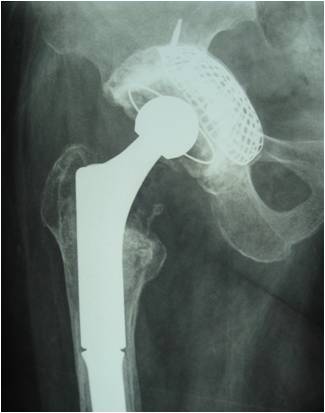

19髋中,18髋的髋臼假体稳定,未发现臼杯在垂直和水平方向大于1mm的移位,也未发现髋臼假体外展角的改变(图1-3)。有1例PaproskyⅢB型患者出现金属网及髋臼杯明显移位等影像学松动表现:术后12月随访时,髋臼上移16.8mm,内移4.7mm;术后28月时,髋臼上移22.7mm,内移5.8mm,髋臼假体外展角较术后减小2.2°(图4-6)。但患者髋关节疼痛不明显,日常生活中能无需手杖独立行走,拒绝再次翻修手术。

图1 全髋关节置换术后无菌松动,髋臼PaproskyⅢA型骨缺损

图2 术后6周,臼底缺损用金属网封闭

图3 术后36月 异体骨整合良好